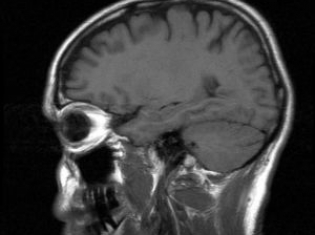

Researchers from Sweden's Uppsala University identified an important aspect of pediatric brain cancer, finding that even when cells were given the same cancer-causing genetic mutation, the tumor did not always turn out the same way.